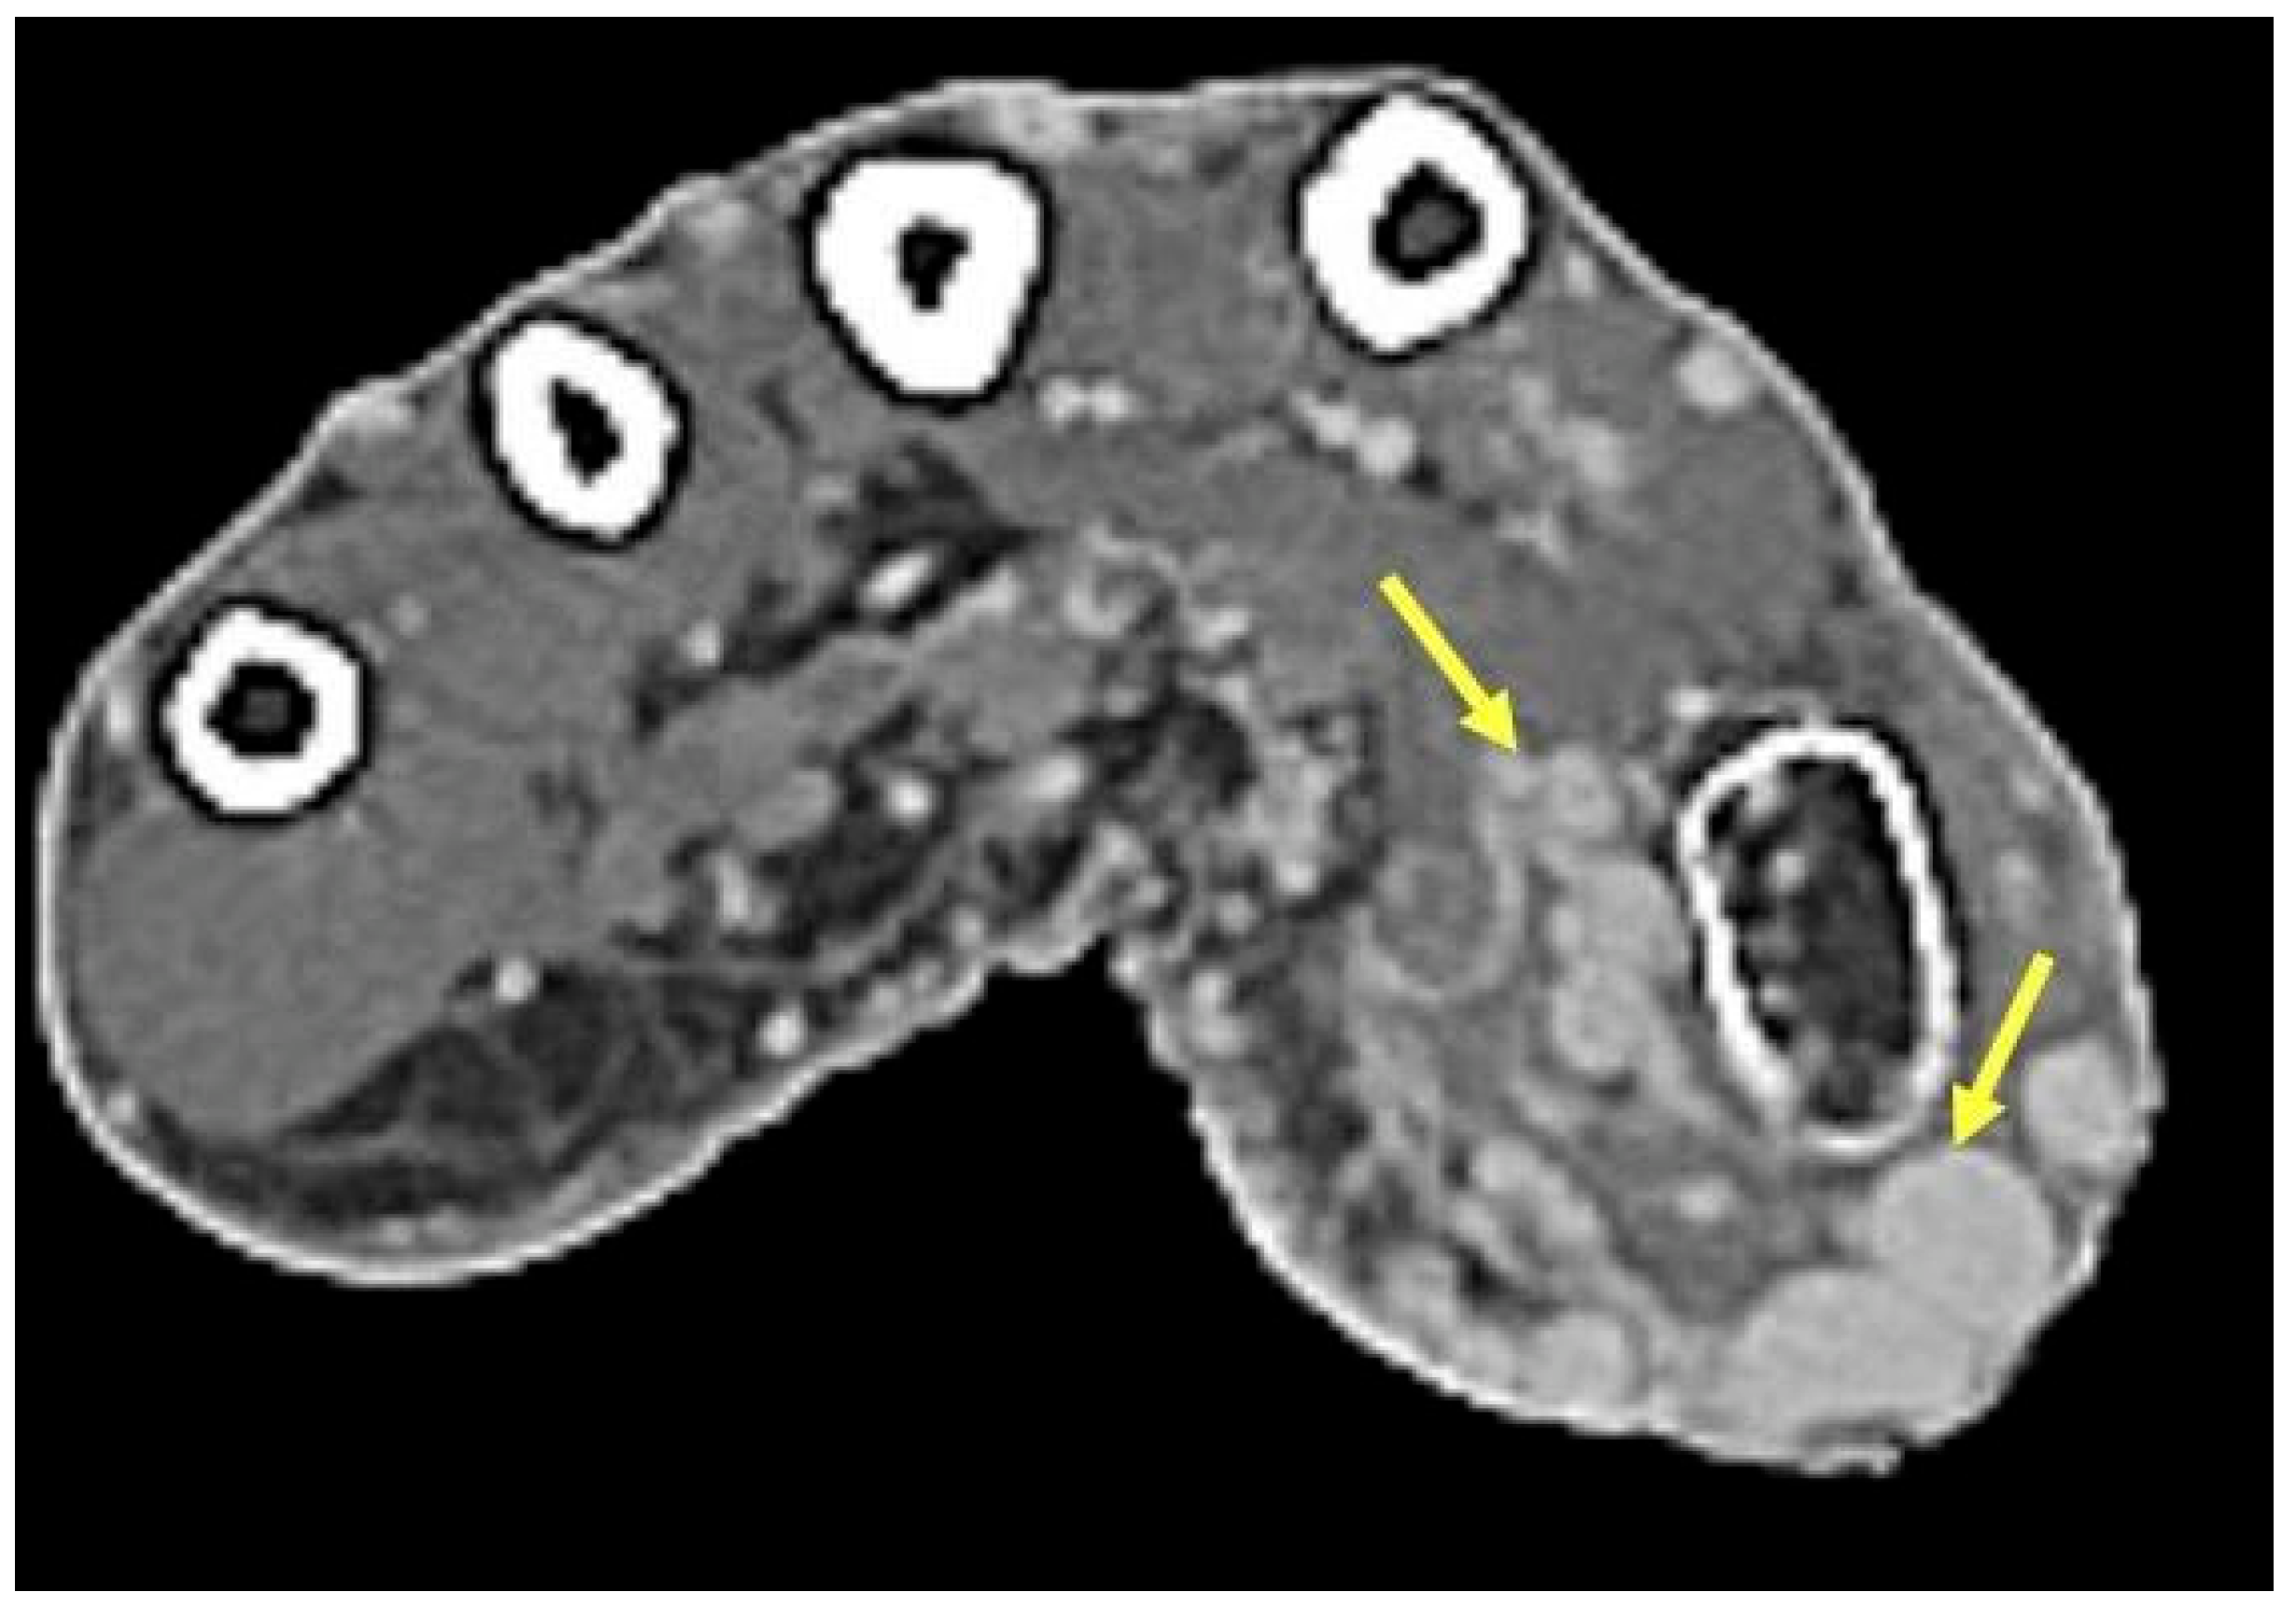

2.9. Infectious Tenosynovitis

2.9.1. Clinical Features

2.9.2. Imaging Appearance